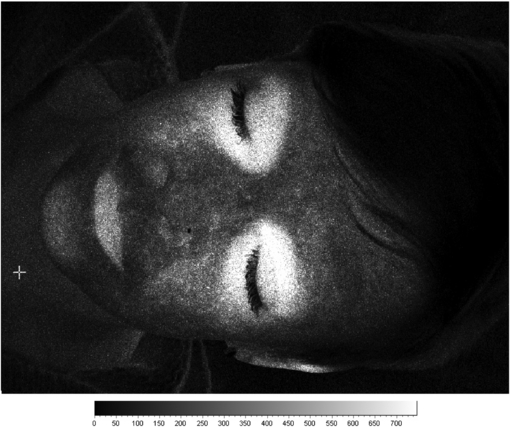

3.1. Imaging PPG

Photoplethysmography imaging (iPPG) is a non-contact imaging method for mapping cardiac synchronous pulsations i.e. perfusion across an area of tissue. iPPG has various forms and can be single wavelength field illumination (near infrared) or dual wavelength illumination (both red and near infrared). iPPG can also be used to determine oxygen saturation by employing algorithms and empirical formulae similar to that of traditional single site contact pulse oximetry. iPPG mapping of pulsatility represents the regional perfusion for the superficial blood vessels including the microcirculation. iPPG has capability for high resolution, fast scanning speeds and can ultimately be of low-cost. The technique can be unreliable where there is significant movement artefact, and correction algorithms are a key part of ongoing technology development. Currently, the literature on iPPG relates to technical advances rather than clinical utility and validity. One very important area with significant commercial potential is its translation to the very low-cost webcam platform. Examples of cardiac synchronous waveforms that can be obtained from the forehead site with iPPG are shown in figure 16.

The detector technology usually comprises a high sensitivity CMOS camera which is held at a fixed distance, e.g. 10–20 cm from the tissue, to measure the variations in light (typically 2–5% of overall reflected light). Images can be collected at rates of tens of frames per second (fps), enabling the pulsatile components to be extracted without aliasing. Image processing comprises various stages, including band-pass filtering and averaging of regions of interest (ROI). The time-varying intensity modulation is strongly affected by relative movement of the camera and body so image processing methods are used to reduce the effect of motion artefacts e.g. by averaging of pixels or Fourier analysis techniques (Wieringa et al 2005, Verkruysse et al 2008). Other centres have experimented with lock-in amplifiers to improve the signal-to-noise ratio (Kamshilin et al 2011). The sensitivity of modern systems allows measurements to be made using very low cost webcams and distances from camera to measurement surface can now typically be 1 m (Rubins et al 2011) (figure 17).

Standard image High-resolution imageEarly iPPG imaging systems were limited by low frame sampling rates, restricting their clinical use, for example in the assessment of pulse rate and its variability. Developments have been promising in terms of speed and sensitivity. The key physiological parameters i.e. respiration rate, heart and also pulse rate variability (PRV) derived from the iPPG datasets can yield statistically comparable results to those acquired using a contact PPG sensor (Sun et al 2013). Advanced physiological monitoring has been reported by Hu et al (2009, 2010) using opto-physiological modelling to extract information on superficial and deeper tissue blood volume perfusion levels (figure 18).